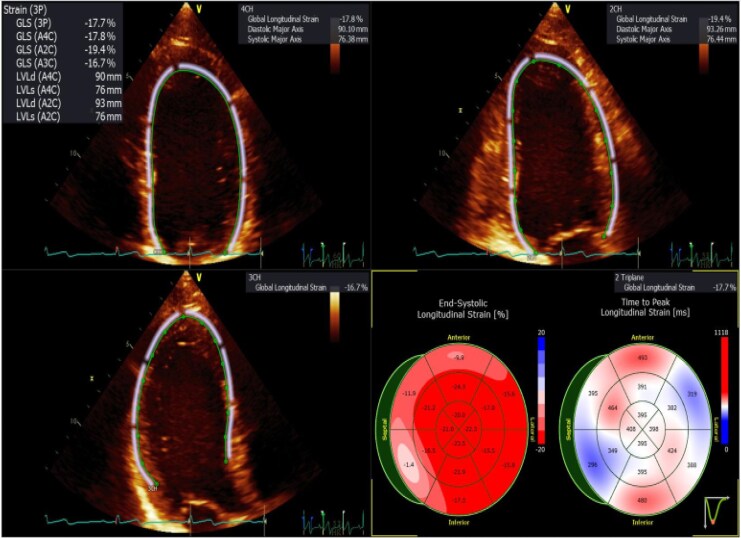

目的:左室(LV)全局纵向应变(GLS)是检测亚临床左室收缩功能障碍的敏感指标,但获取和分析的可变性可能限制其临床应用。我们研究了不同二维和三维超声心动图采集方法和后处理平台的左室GLS的准确性、可变性和相关性。方法和结果:在这项前瞻性研究中,我们分析了254例连续接受临床指示超声检查的患者(平均年龄55±16岁,60%为女性)。GLS测量采用多种二维采集方法(三拍和单拍)和三维采集方法。使用供应商特定的(EchoPac)和供应商中立的(TomTec-Arena)软件进行分析。使用Pearson相关、类内相关系数(ICCs)和Bland-Altman分析评估方法之间的相关性和一致性。在不同的获取方法和不同的软件平台之间,GLS值是高度一致的。平均GLS值分别为-19.4±3.3 (2D-A)、-19.2±3.3 (2D-B)、-19.1±3.5 (3P)和-14.8±4.1 (3D)。2D GLS的观察者内部和观察者之间的可变性很低(ICC >0.9),表明具有良好的再现性。然而,3D GLS值明显低于2D(平均差值-4.3%),相关性仅为中等(r = 0.66),表明2D和3D GLS值不可互换。结论:LV GLS是一种可靠的评价LV功能的方法,在不同的采集和分析方法中具有较强的重复性。然而,3D GLS一直较低,不应与2D测量交替使用。这些发现强调了在比较2D和3D方法的GLS值时需要持续的标准化和谨慎。

Methods and results: In this prospective study, we analyzed 254 consecutive patients (mean age 55 ± 16 years, 60% female) undergoing clinically indicated echo. GLS was measured using multiple 2D acquisition methods (three beats and single beat) and 3D. Analyses were performed using both vendor-specific (EchoPac) and vendor-neutral (TomTec-Arena) software. Correlations and agreement between methods were assessed using Pearson correlation, intraclass correlation coefficients (ICCs), and Bland-Altman analyses.GLS values were highly consistent across the acquisition methods and between software platforms. Mean GLS values were -19.4 ± 3.3 (2D-A), -19.2 ± 3.3 (2D-B), -19.1 ± 3.5 (3P), and -14.8 ± 4.1 (3D). Intra- and interobserver variability for 2D GLS was low (ICC >0.9), indicating excellent reproducibility. However, 3D GLS values were significantly lower than 2D (mean difference -4.3%), with only moderate correlation (r = 0.66), suggesting that 2D and 3D GLS values are not interchangeable.